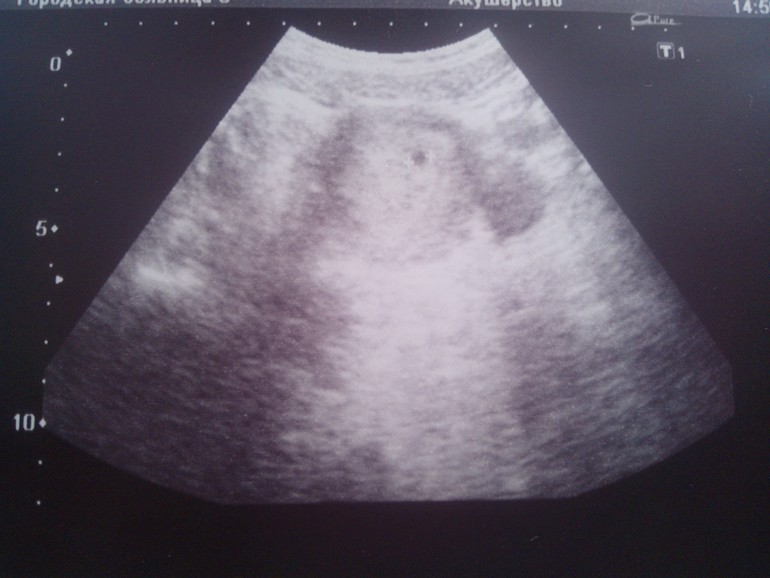

Вот он - наш малыш! ))) Сегодня мы познакомились с ним. Он на месте и это очень мне успокоило. Рост уже целых 4мм - рослый малый ))) Сердечко стучит 113 (или 130 не расслышала) ударов в минуту. Ни чего про тонус, отслойки и прочую гадость врач мне не сказала - значит всё хорошо. Завтра встанем на чет ))))

Папа тоже был рад знакомству. У него сегодня день рождения и мы устроили ему вот такой вот подарок )))